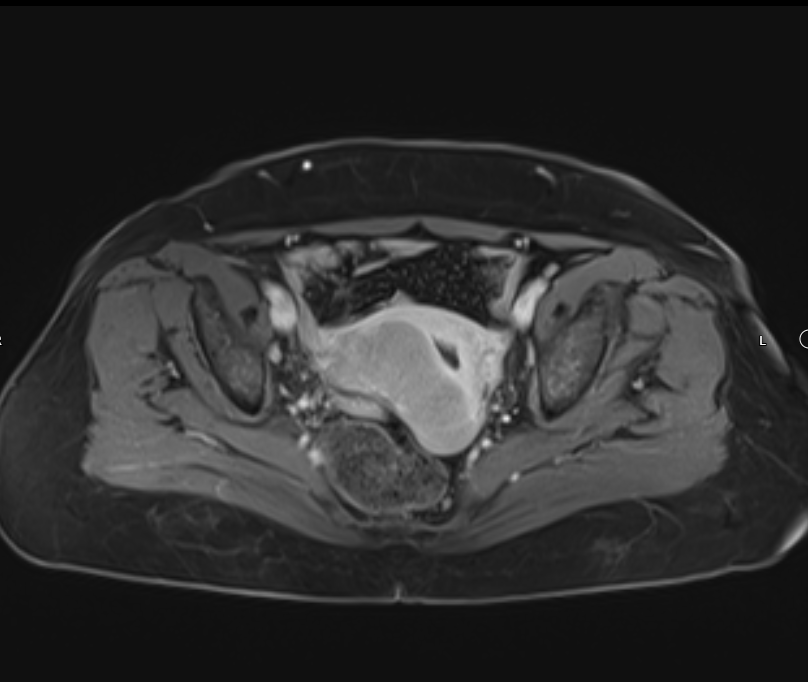

Bulky uterus, endometrial lining thickness 2mm, occupied by clear avascular fluid , mostly due to mass effect , Presence of hypoechoic solid mass 68x48mm ,vascular on color Doppler , Color Score 4 (Hyper vascular) , within right sided posterior submucosal subserosal region , associated with other two smaller masses seen on the anterior wall , their sizes are 19x18mm& 8x12mm (Metastasis? Lymphoma ??) or other suspicious masses

Associated with Presence of pathological lymph node in the right para iliac region size 35x24mm& other pathological lymph node in the left para iliac region 35x21mm , lymphoma or secondary metastasis can not be excluded

Atrophied both ovaries, bilateral few tiny follicles, their sizes less than 2mm, no dominate follicle, nor mass

No free pelvic fluid